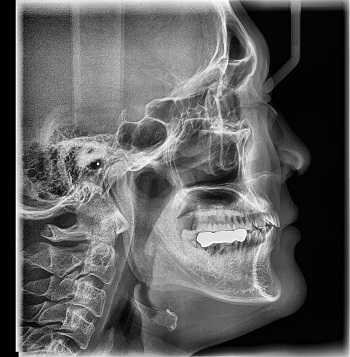

В основе физики работы рентген-аппарата лежат просвечивающие способности рентгеновских лучей. Получение плоского двухмерного изображения основано на ослаблении рентгеновского излучения при его прохождении через различные ткани. При рентген-сканировании пучок излучения, проходя через ткани организма, которые обладают различной плотностью, рассеивается и тормозится. Таким образом, на пленке возникают изображения разной степени интенсивности. Лучевая нагрузка при рентгенографии небольшая, но она всегда есть и может составлять от 0,1 до 1 мЗв. Поэтому рентгенография запрещена для беременных женщин, а здоровому человеку рентген можно делать 1- 2 раза в год.

Кроме дозы облучения у рентгеновского сканирования есть один существенный диагностический недостаток - плоская картинка. Поскольку рентген изображения - это тень ткани на пленке, объемно оценить органы и структуры человеческого тела с помощью рентгена не получается.

Рентгенография

Принцип работы рентгеновского аппарата заключается в том, что рентгеновские лучи, проходя через разноплотную среду исследуемой области, по-разному ослабляются: более плотная костная ткань в значительной степени поглощает рентгеновское излучение, менее плотная подкожно-жировая клетчатка ослабляет его в небольшой степени, а воздух, содержащийся в околоносовых пазухах или легких, не задерживает совсем. Эти неравномерно ослабленные пучки рентгеновских лучей, попадая на светочувствительный слой пленки, формируют рентгенограмму — изображение, которое отображает все структуры исследуемой области, наслаивая их друг на друга. При этом получаемый снимок позволяет определить форму, размеры и строение исследуемой области, выявить или заподозрить структурные нарушения, а исследование в двух или нескольких проекциях позволяет определить локализацию выявленных изменений. Чаще всего рентгенография используется для исследования костей, легких, почек, кишечника.

C самого начала существования этот метод диагностики вызывал у пациентов множество вопросов по поводу воздействия рентгеновского излучения на организм. На сегодняшний день специалисты подтвердили вред рентгена и его способность влиять на развитие нежелательных процессов в организме. Тем не менее, этот метод лучевой диагностики продолжает пользоваться спросом, поскольку требует минимальных затрат.